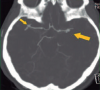

Management of multiple intracranial aneurysms

Marco Gonzáles-Portillo S., Luis Contreras M., Marco Chipana S., Luis Huamán T., Pedro Soto P.